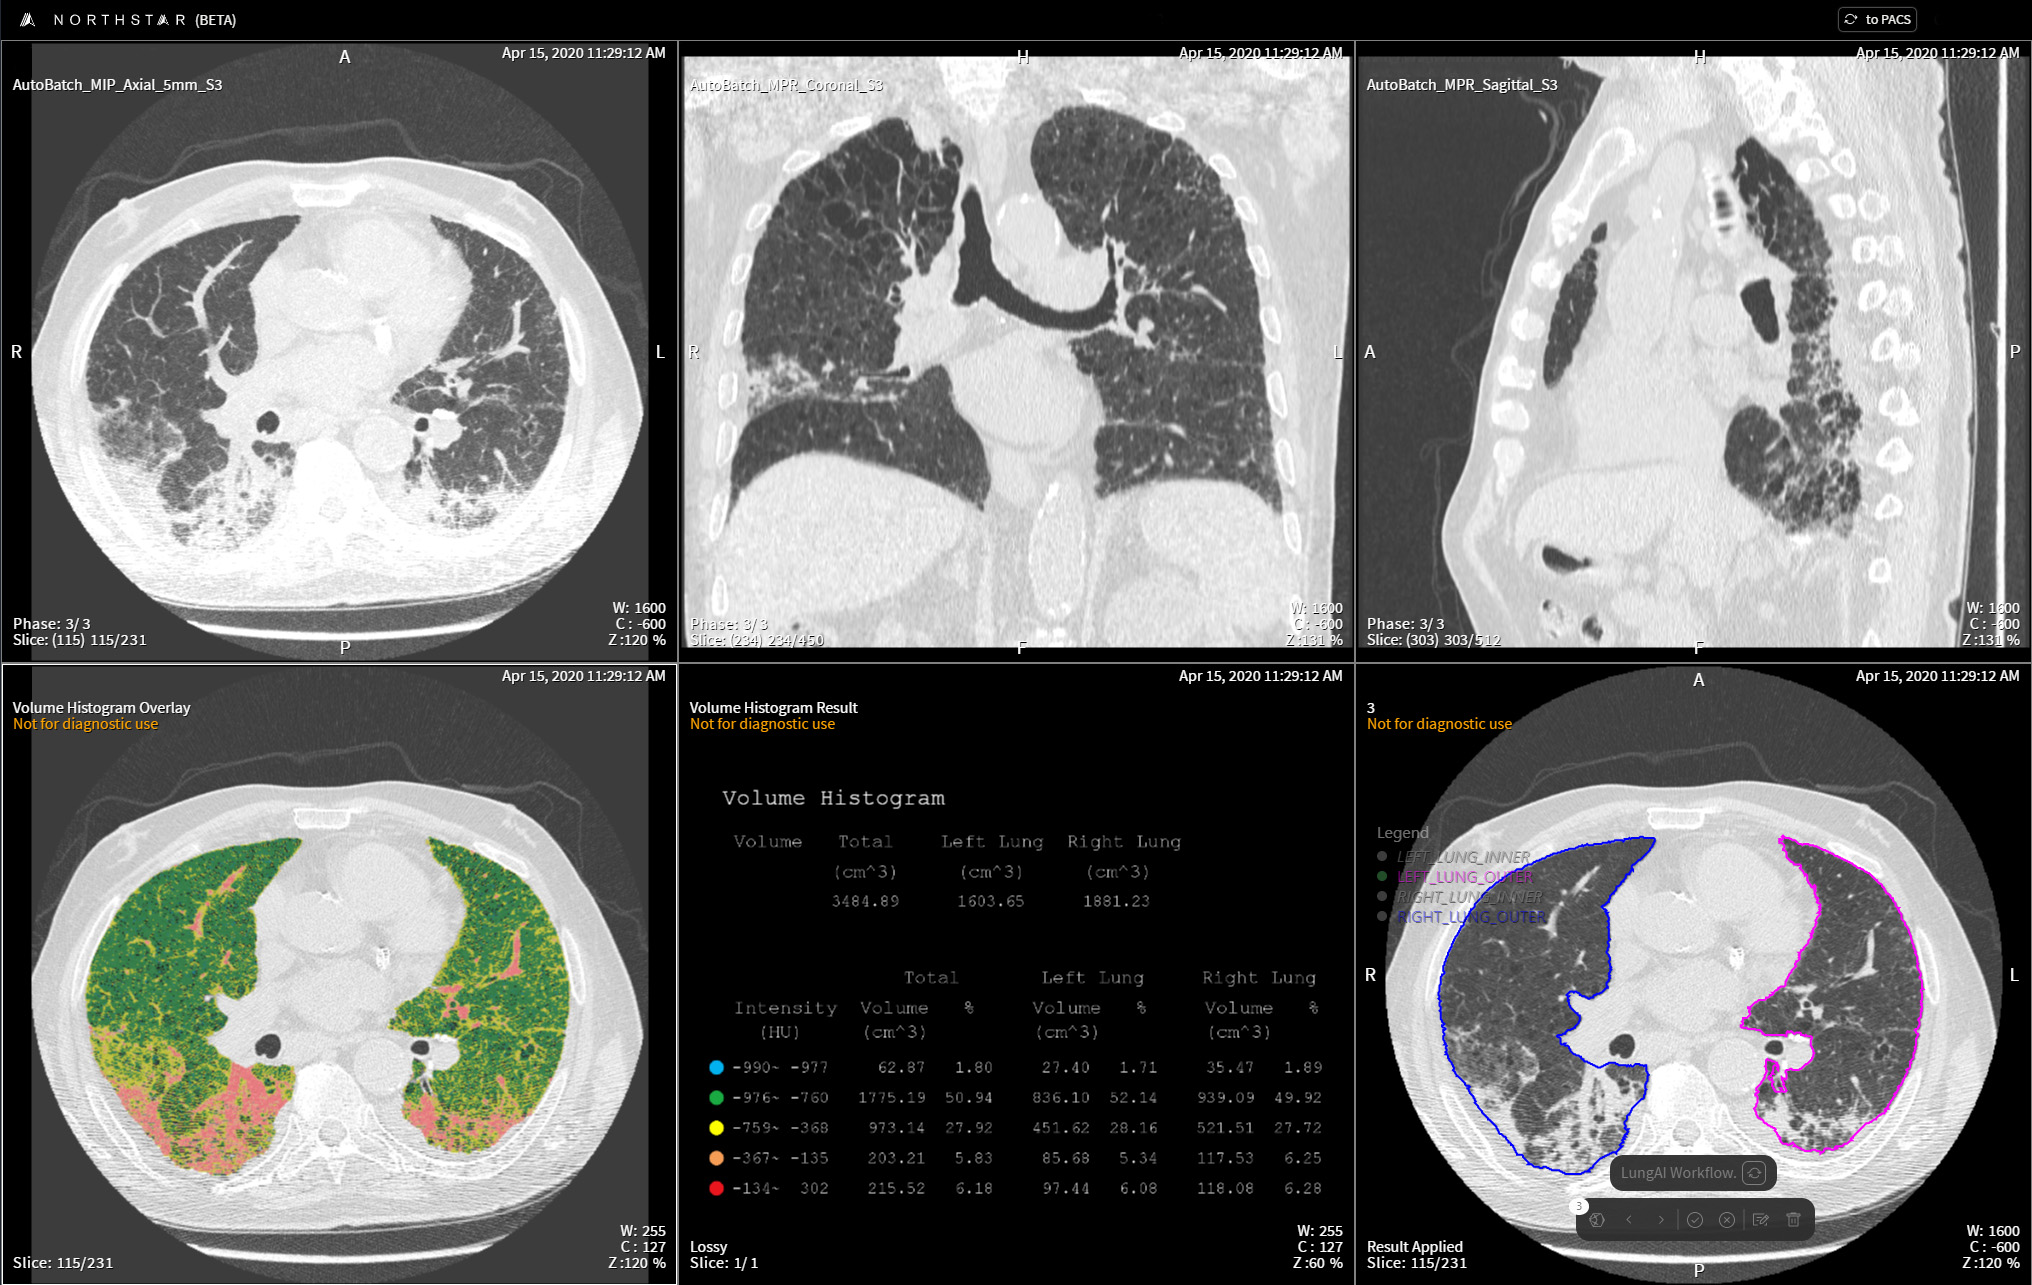

Lung Density Analysis™ Inspiration Imbio

from www.imbio.com

Lung Density Analysis™ Functional Imbio What Is A Lung Density Test Hyperdense refers to an area on the ct scan that appears brighter or denser than the surrounding. This technique entails quantifying the density of. lung density analysis is a medical imaging method employed for evaluating lung structure and function. However, lung density depends on the state of inflation. spirometry is a simple test used to help diagnose and. What Is A Lung Density Test.

Lung Density Analysis™ Inspiration Imbio What Is A Lung Density Test This technique entails quantifying the density of. A blood test can show other conditions that can cause similar symptoms to copd, such as a low iron level (anaemia) and a high concentration of red blood cells. spirometry is a simple test used to help diagnose and monitor certain lung conditions by measuring how much air you can. Hyperdense refers. What Is A Lung Density Test.